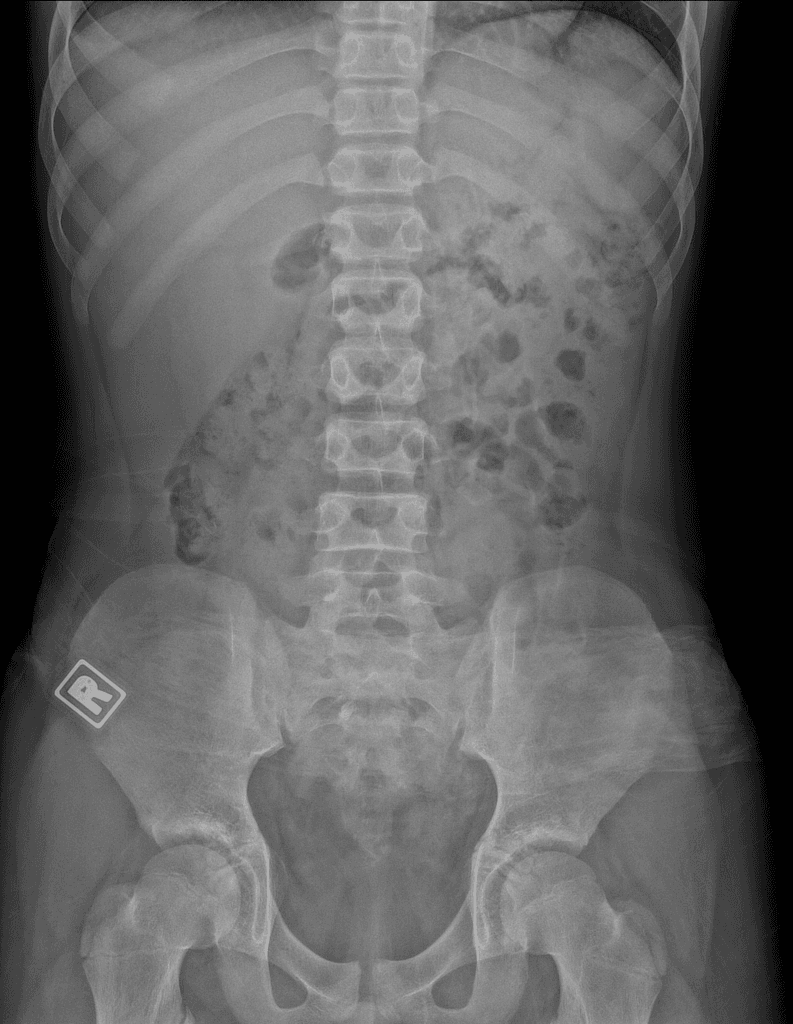

Đau đầu mới xuất hiện và liệt nửa người trái ở bệnh nhân đang điều trị ung thư phổi tế bào không nhỏ.

Phát hiện nhiều nốt (nodule) và khối (mass) ở vùng trên lều, trong đó tổn thương lớn nhất nằm ở thùy chẩm phải, kích thước khoảng 34 x 29 x 30 mm.

Các tổn thương ở nhu mô não (brain parenchyma), sọ vòm (calvarium) và màng não (meninges) vùng trán trái phù hợp với di căn nội sọ (intracranial metastases).

Di căn nội sọ (intracranial metastases)